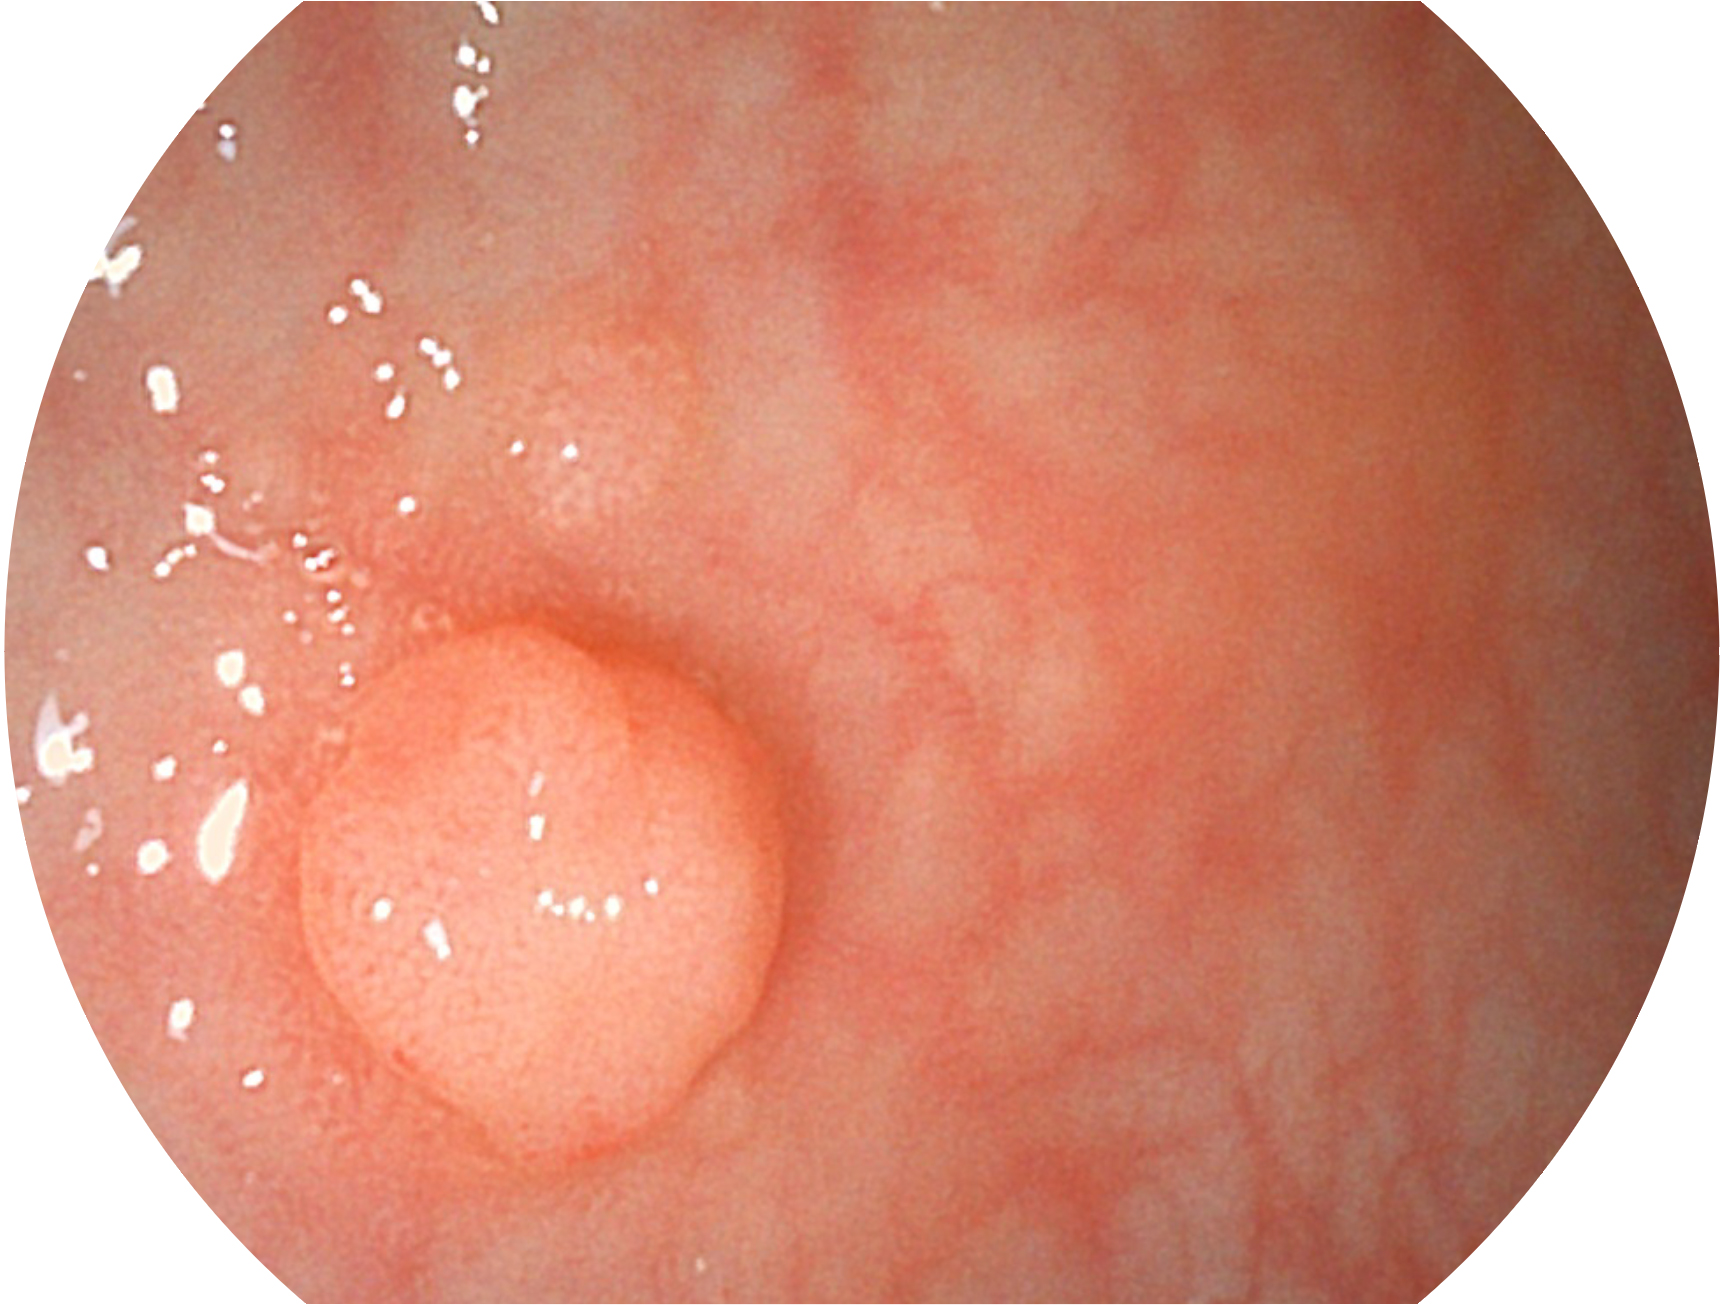

竞技宝(JJB)官方网站新开发的内镜染色技术,主要是基于多波长LED 光源的开发,VLS-55Q 四波长LED 光源是由四个不同颜色的LED光按照相应照明模式所规定的特定发光比例进行合束后形成,合束后形成的照明光的光谱由红光、绿光、蓝光及蓝紫光这四个不同的波段范围构成。具有更高光谱自由度,通过光谱比例的控制,实现了聚谱成像技术,英文全称为“Spectral Focused Imaging, SFI”,缩写为“SFI”和光电复合染色成像技术,英文全称为“Versatile Intelligent Staining Technology, VIST”,缩写为“VIST”。